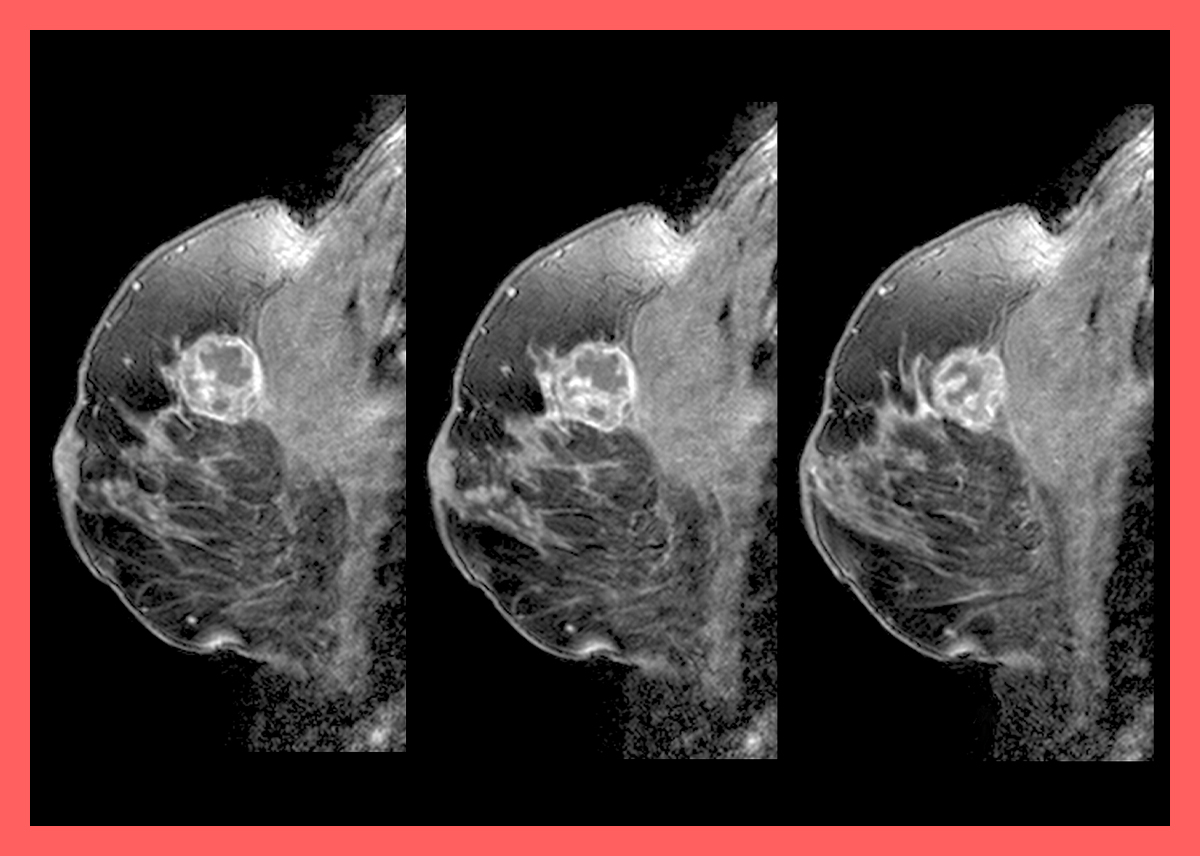

매년 발표되는 국가암등록사업 연례 보고서에 따르면 유방암이 암발생 순위 5순위에 들어 상당히 많이 걸리는 것으로 나타났으며 여성에게 있어서는 갑상선암, 대장암, 위암 등을 제치고 가장 많은 암 발병률을 보이고 있습니다. 유방암 역시 세포 이상이 생겨 계속 분열되고 늘어나면서 조직이 증가하는데 이때 커진 조직을 종양이라고 부르는데 유방 내 종양이 생기는 것을 바로 유방암이라고 합니다.

유방암은 유방에서 발생되는 악성 종양 모두를 칭하는 말입니다. 특히 유방 밖으로 종양이 퍼져 다른 장기나 림프절로 전이되고 성장과 증식속도가 빠른 것이 특징입니다. 이러한 유방암의 원인은 정확하게 확인되지 않았으나 유전적 요인과 환경적 요인을 유방암 발병 원인으로 보고 있습니다. 특히나 유방암 환자의 10% 정도는 유전적 요인이 있다고 알려졌으니 가족력이 있는 경우 유방암 검진을 주기적으로 받아보는 것이 좋겠습니다.